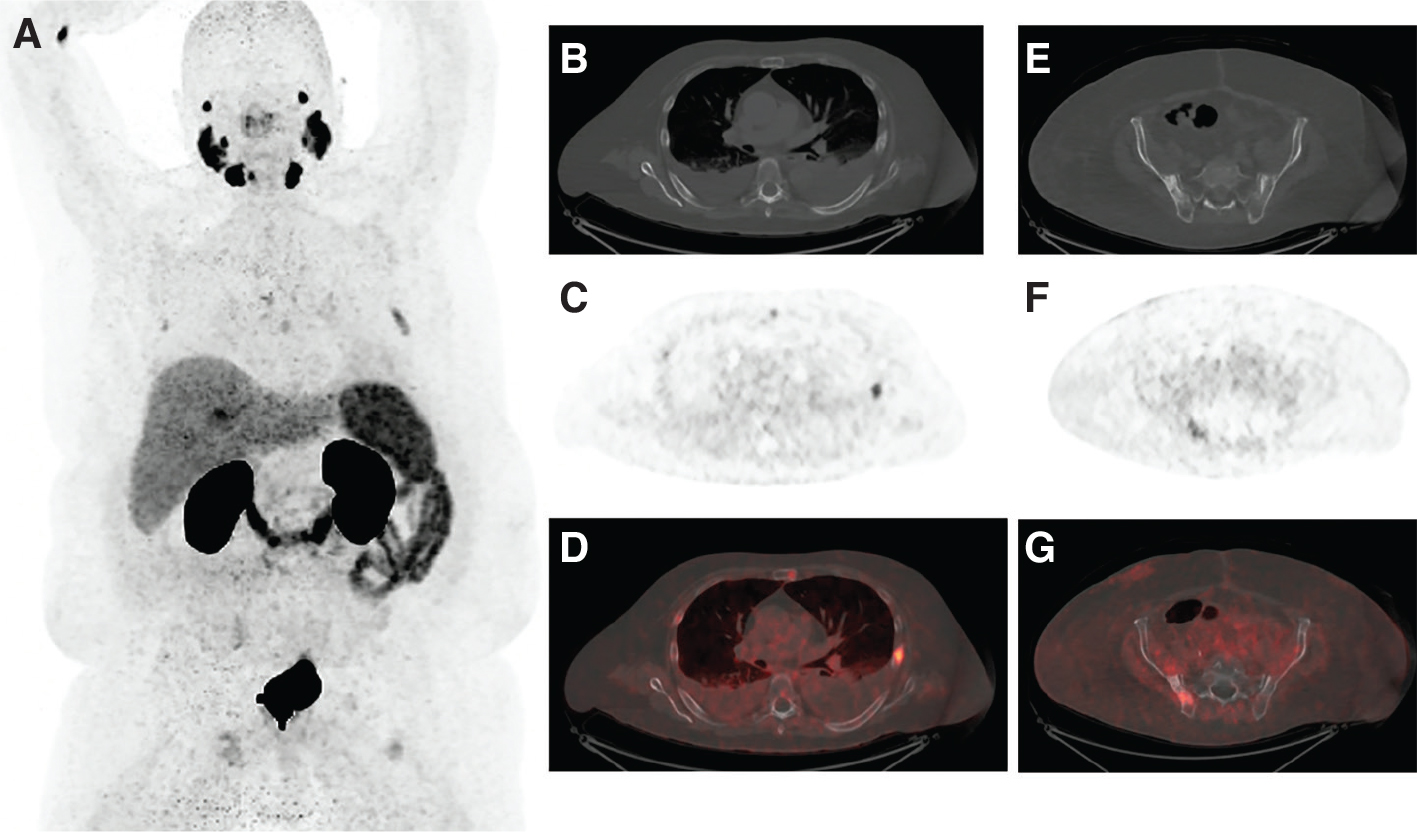

ROLE OF PSMA PET IMAGING

Lesion-specific PSMA expression is evaluated with PSMA PET imaging and is a key determinant for PSMA RLT eligibility. For PSMA RLT to be beneficial, metastatic lesions must demonstrate sufficient expression of PSMA (Figure 1). Patients whose metastatic lesions lack significant PSMA expression should not be considered for PSMA RLT, as PSMA receptor expression is required for treatment target localization (Figure 2). Pretreatment PSMA PET may also contain important prognostic information that has been shown to correlate with the degree of response and overall benefit of PSMA RLT. However, there are different definitions of what constitutes PSMA-positive and PSMA-negative disease in currently published PSMA RLT trials (Tables 1 and 2).

Fig 2

Figure 2. An 82-year-old man with metastatic prostate cancer, but with limited PSMA expression of disease, ineligible for 177Lu- PSMA-617 RLT. A. Maximum intensity projection image of 18F-PyL PSMA PET/CT; B. axial CT image of the chest demonstrating one osteoblastic rib lesion and mild uptake in the sternal body and a right-sided rib; C. axial PSMA PET image demonstrating uptake related to the osteoblastic rib lesion and mild uptake in the sternal body and a right-sided rib; D. fused PET/CT images of B and C; E. axial CT image demonstrating an osteoblastic right iliac bone lesion; F. PSMA PET image demonstrating limited uptake associated with the osteoblastic lesion; G. fused images of E and F.

To identify potential PSMA-negative disease, patients should undergo contrast-enhanced CT or MRI of the abdomen and pelvis within a reasonable timeframe surrounding PSMA PET imaging. Treatment may be appropriate for patients with heterogeneous disease on PSMA PET, especially if most of the disease is PSMA positive and the patient has exhausted all other therapeutic options.